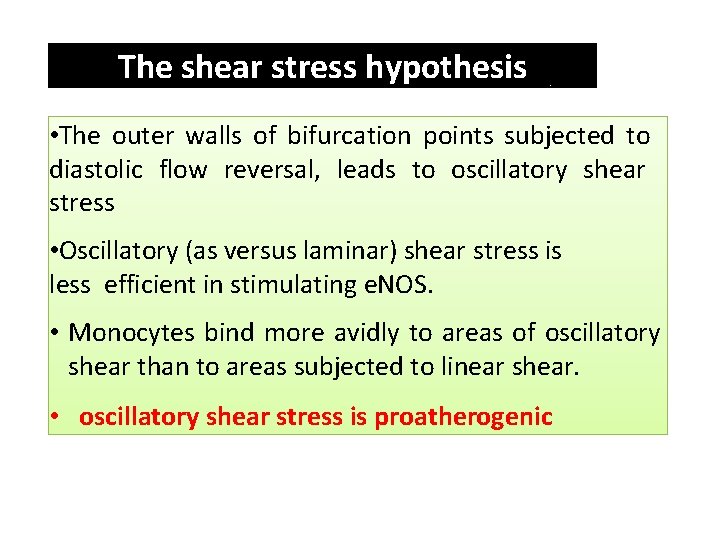

The shear stress hypothesis • The outer walls of bifurcation points subjected to diastolic flow reversal, leads to oscillatory shear stress • Oscillatory (as versus laminar) shear stress is less efficient in stimulating e. NOS. • Monocytes bind more avidly to areas of oscillatory shear than to areas subjected to linear shear. • oscillatory shear stress is proatherogenic